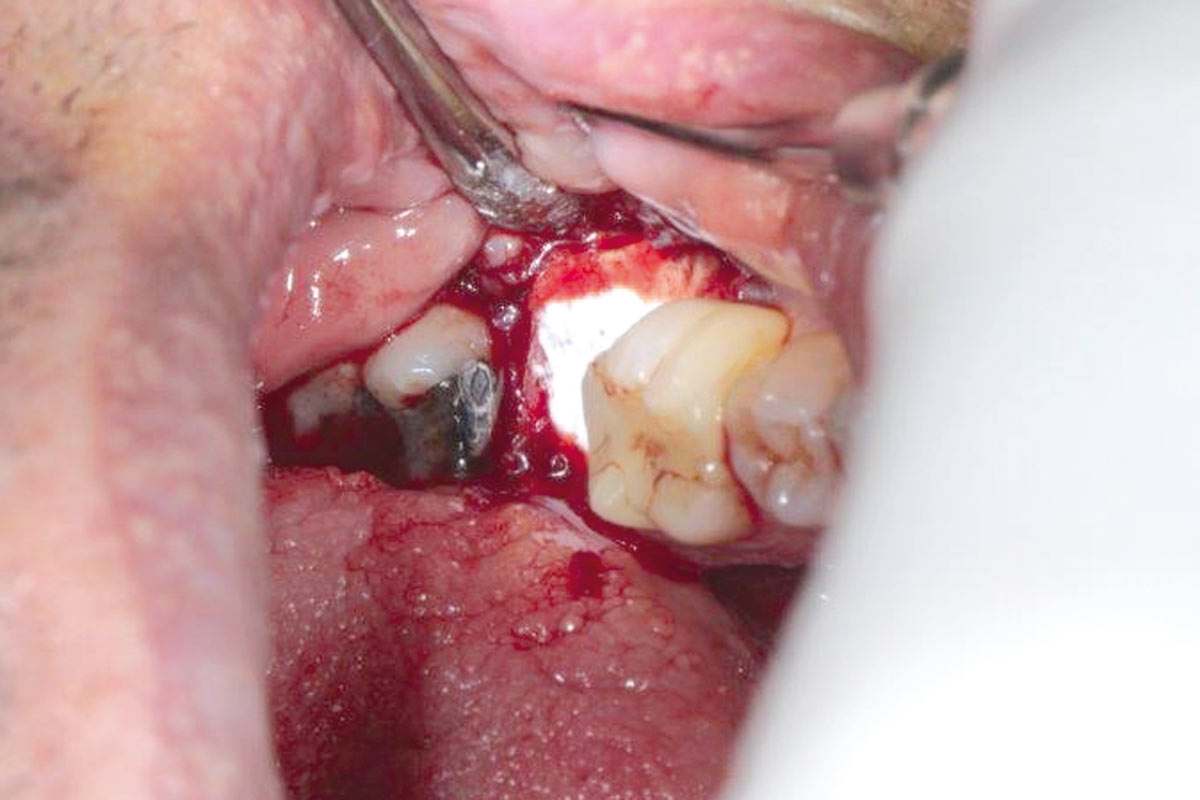

botiss cerabone® & Jason® membrane for GBR - Clinical case by Prof. Dr. Dr. D. Rothamel

Instable bridge situation with abscess formation at tooth #15 after apicoectomy